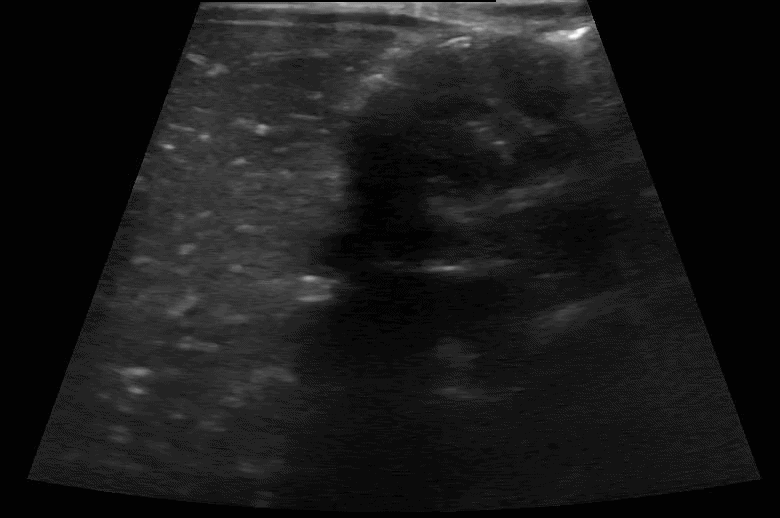

Scanning technique: When evaluating for intussusception with point-of-care ultrasound (POCUS), the infant is placed supine and a high-frequency linear transducer is used initially, with a curvilinear probe available for deeper or larger fields of view. The abdomen is scanned systematically in transverse and longitudinal planes, starting in the right lower quadrant and sweeping through the right upper quadrant, epigastrium, and left abdomen, with particular attention to the periumbilical region and right upper quadrant, where intussusception is most commonly identified. Graded compression is applied to displace bowel gas and improve visualization. On POCUS, intussusception classically appears as a “target” or “donut” sign in the transverse view, characterized by concentric hypoechoic and hyperechoic rings, and as a “pseudokidney” or “sandwich” sign in the longitudinal view. Associated findings may include proximal bowel dilation, free fluid, or absent peristalsis within the involved segment.

Clip 3: Intussusception long axis.